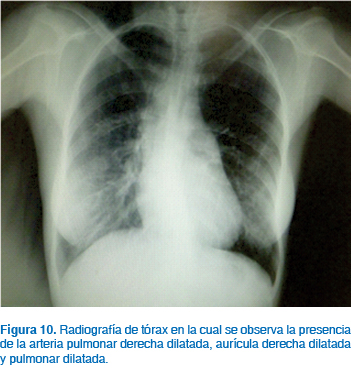

El síndrome de Eisenmenger es la complicación más crítica de las pacientes que presentan algún tipo de defecto cardiaco con cortocircuito13,18,22 (Figuras 9 a 11). Este síndrome se desarrolla a través de los años conforme se incrementa el grado y severidad de la hipertensión pulmonar cuando no existe corrección del defecto inicial. La causa más común para la aparición del síndrome es un gran defecto septal seguido de la persistencia del conducto arterioso. El mecanismo de desarrollo es el siguiente: el aumento del flujo a la circulación pulmonar en un inicio es tolerado por la vasodilatación pulmonar; sin embargo, conforme pasa el tiempo existe aumento de las resistencias vasculares pulmonares por cambios en la íntima de estos vasos, aumentando la resistencia hasta niveles severos; la dificultad para la perfusión pulmonar genera aumento de la presión en la arteria pulmonar, ventrículo derecho y aurícula derecha, generando dilatación primero y luego hipertrofia de estas cavidades. En estas circunstancias, la presión en las cavidades derechas cardiacas puede superar las presiones de las cavidades izquierdas venciendo las resistencias vasculares sistémicas e invirtiendo el flujo del cortocircuito, siendo inicialmente de izquierda a derecha para posteriormente ser de derecha a izquierda. En estas condiciones, parte del gasto cardiaco derecho pasa a la circulación izquierda sin pasar por los pulmones, generándose cianosis en la paciente.13

El síndrome de Eisenmenger se define cuando ocurren los siguientes cambios: hipertensión pulmonar con un incremento de las resistencias vasculares pulmonares mayor a 3 mmHg/L/min/m2, una presión sistólica de la arteria pulmonar mayor a 30 mmHg en ejercicio o mayor a 25 mmHg en reposo y una presión capilar pulmonar menor de 15 mmHg; estas circunstancias en presencia de inversión del cortocircuito intracardiaco o que sea bidireccional, se dan en una paciente en la que inicialmente era de izquierda a derecha.6

La disnea de esfuerzo es el síntoma de presentación más frecuente, seguido por palpitaciones, edema, fatiga, hemoptisis, síncope y cianosis progresiva, además de insuficiencia cardiaca derecha en fases avanzadas.6,13 El síndrome de Eisenmenger es una importante causa de muerte en obstetricia; en países desarrollados, la mortalidad reportada es de un 30% y ocurre con frecuencia en la resolución del embarazo, en el puerperio inmediato, sobre todo en la primera semana; sin embargo, existen publicaciones que señalan una mortalidad de 50 a 80%.10 Generalmente, los síntomas de falla cardiaca ( New York Heart Association > 2), reducción de la función ventricular izquierda, problemas cardiovasculares durante el embarazo e insuficiencia severa de la válvula pulmonar, especialmente combinada con reducción de la función ventricular derecha, están asociados con incremento en riesgo para la mujer embarazada.19